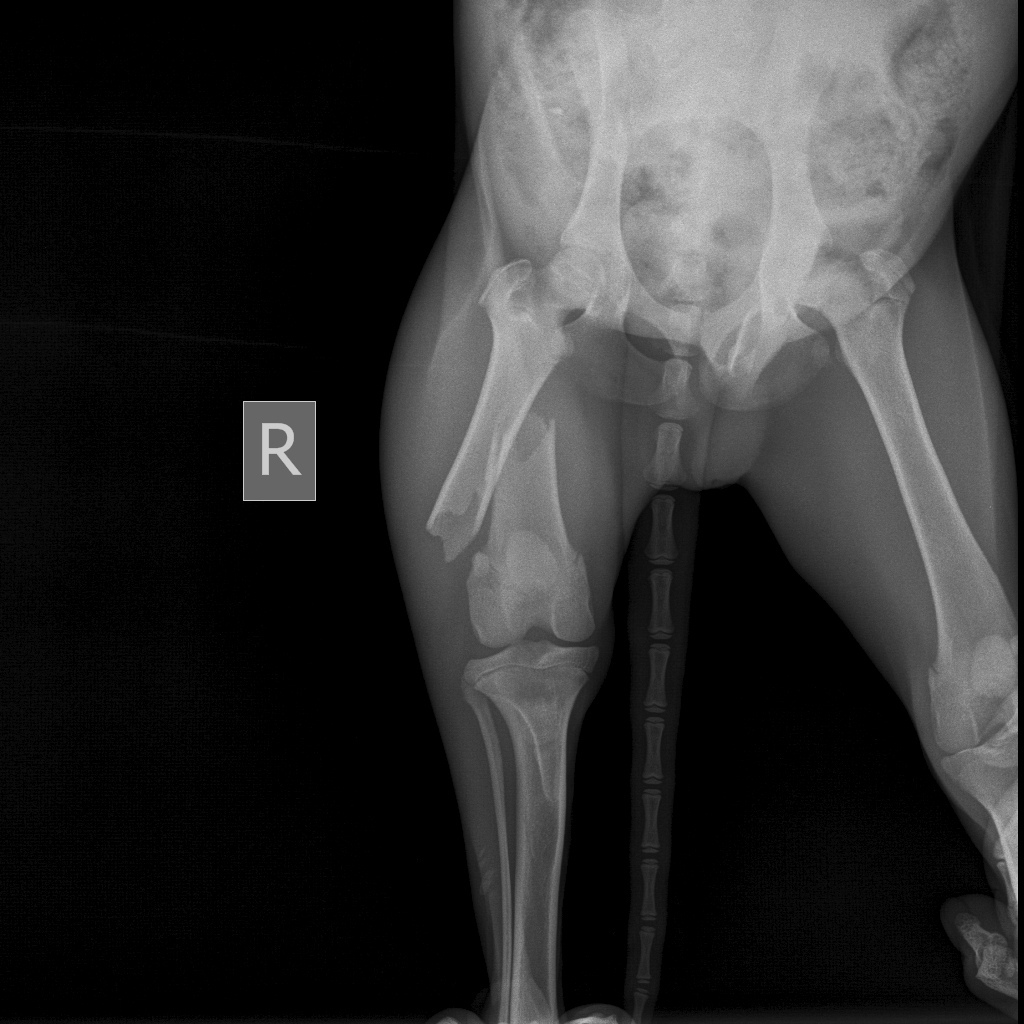

У клініцы паведамілі, што жывёла моцна знясілена і са зламаным сцягном. Магчыма, яго нехта сістэматычна збіваў.